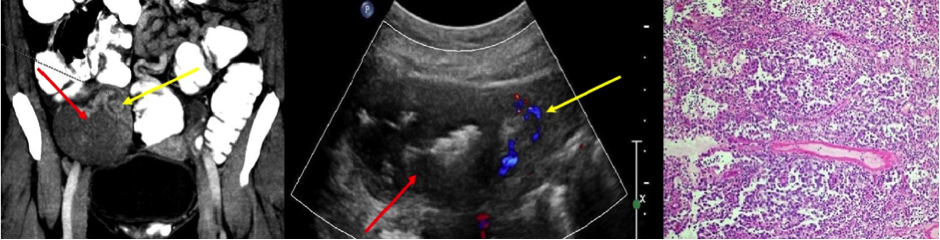

Poster abstracts – FPM Centenary Conference – 7th December 2018

14a

940 × 240 pixels